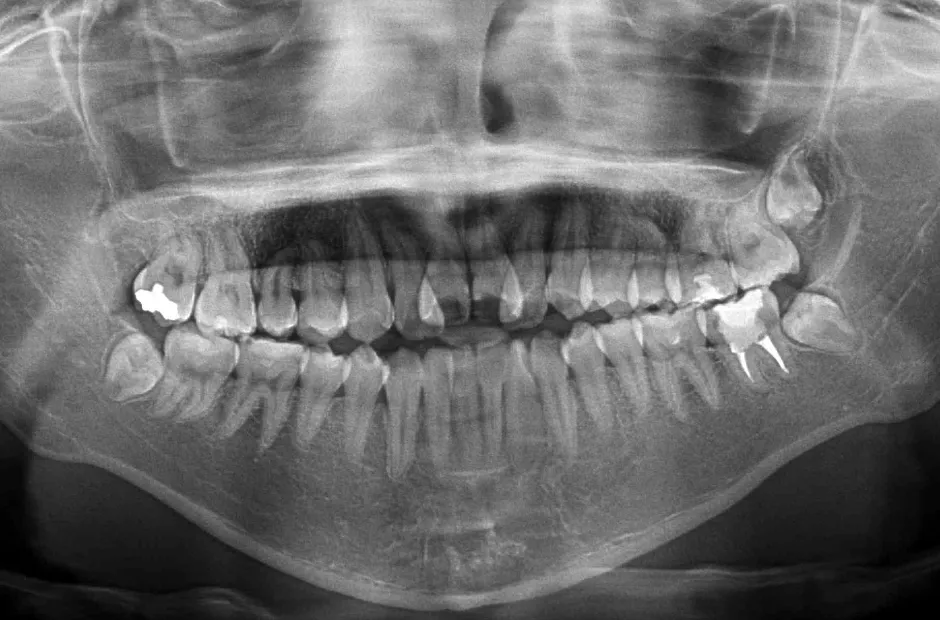

| 診断名・主訴 | 下顎前突、叢生 |

|---|---|

| 年齢・性別 | 23歳・女性 |

| 治療期間・回数 | 3年 |

| 治療に用いた主な装置 | 上顎5,5 下顎4,4 |

| 抜歯部位 | 舌側矯正 |

| 治療費 | 100万円(税抜) |

| リスク・副作用 | 装置による違和感・疼痛・歯肉退縮・歯根吸収・虫歯のリスクなど |

治療前

治療中

治療後